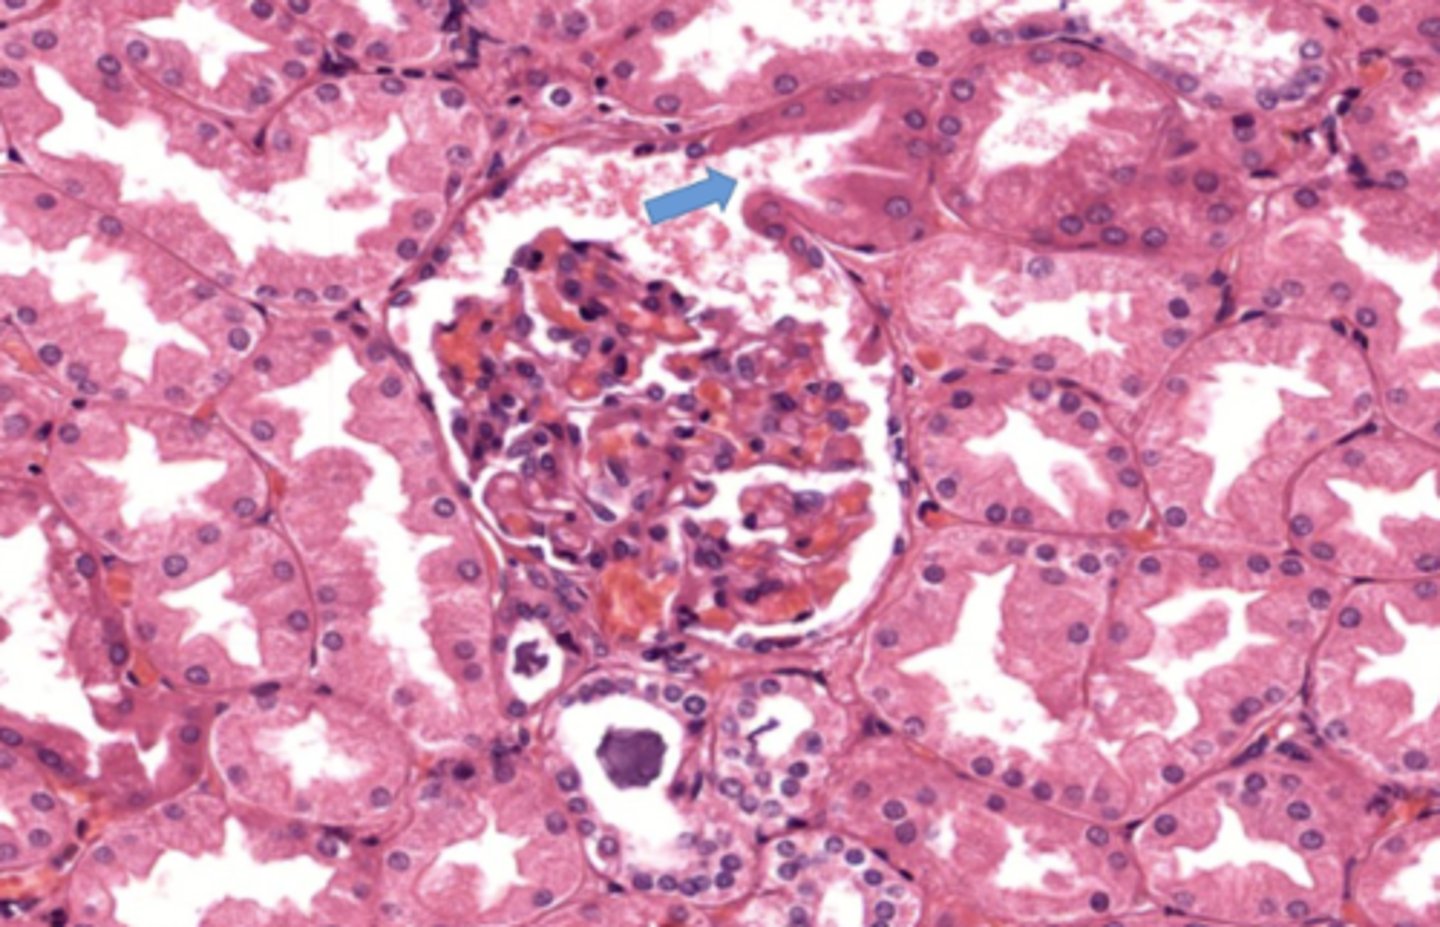

glomerulus

What cells does the glomerulus contain

mesangial cells and podocytes